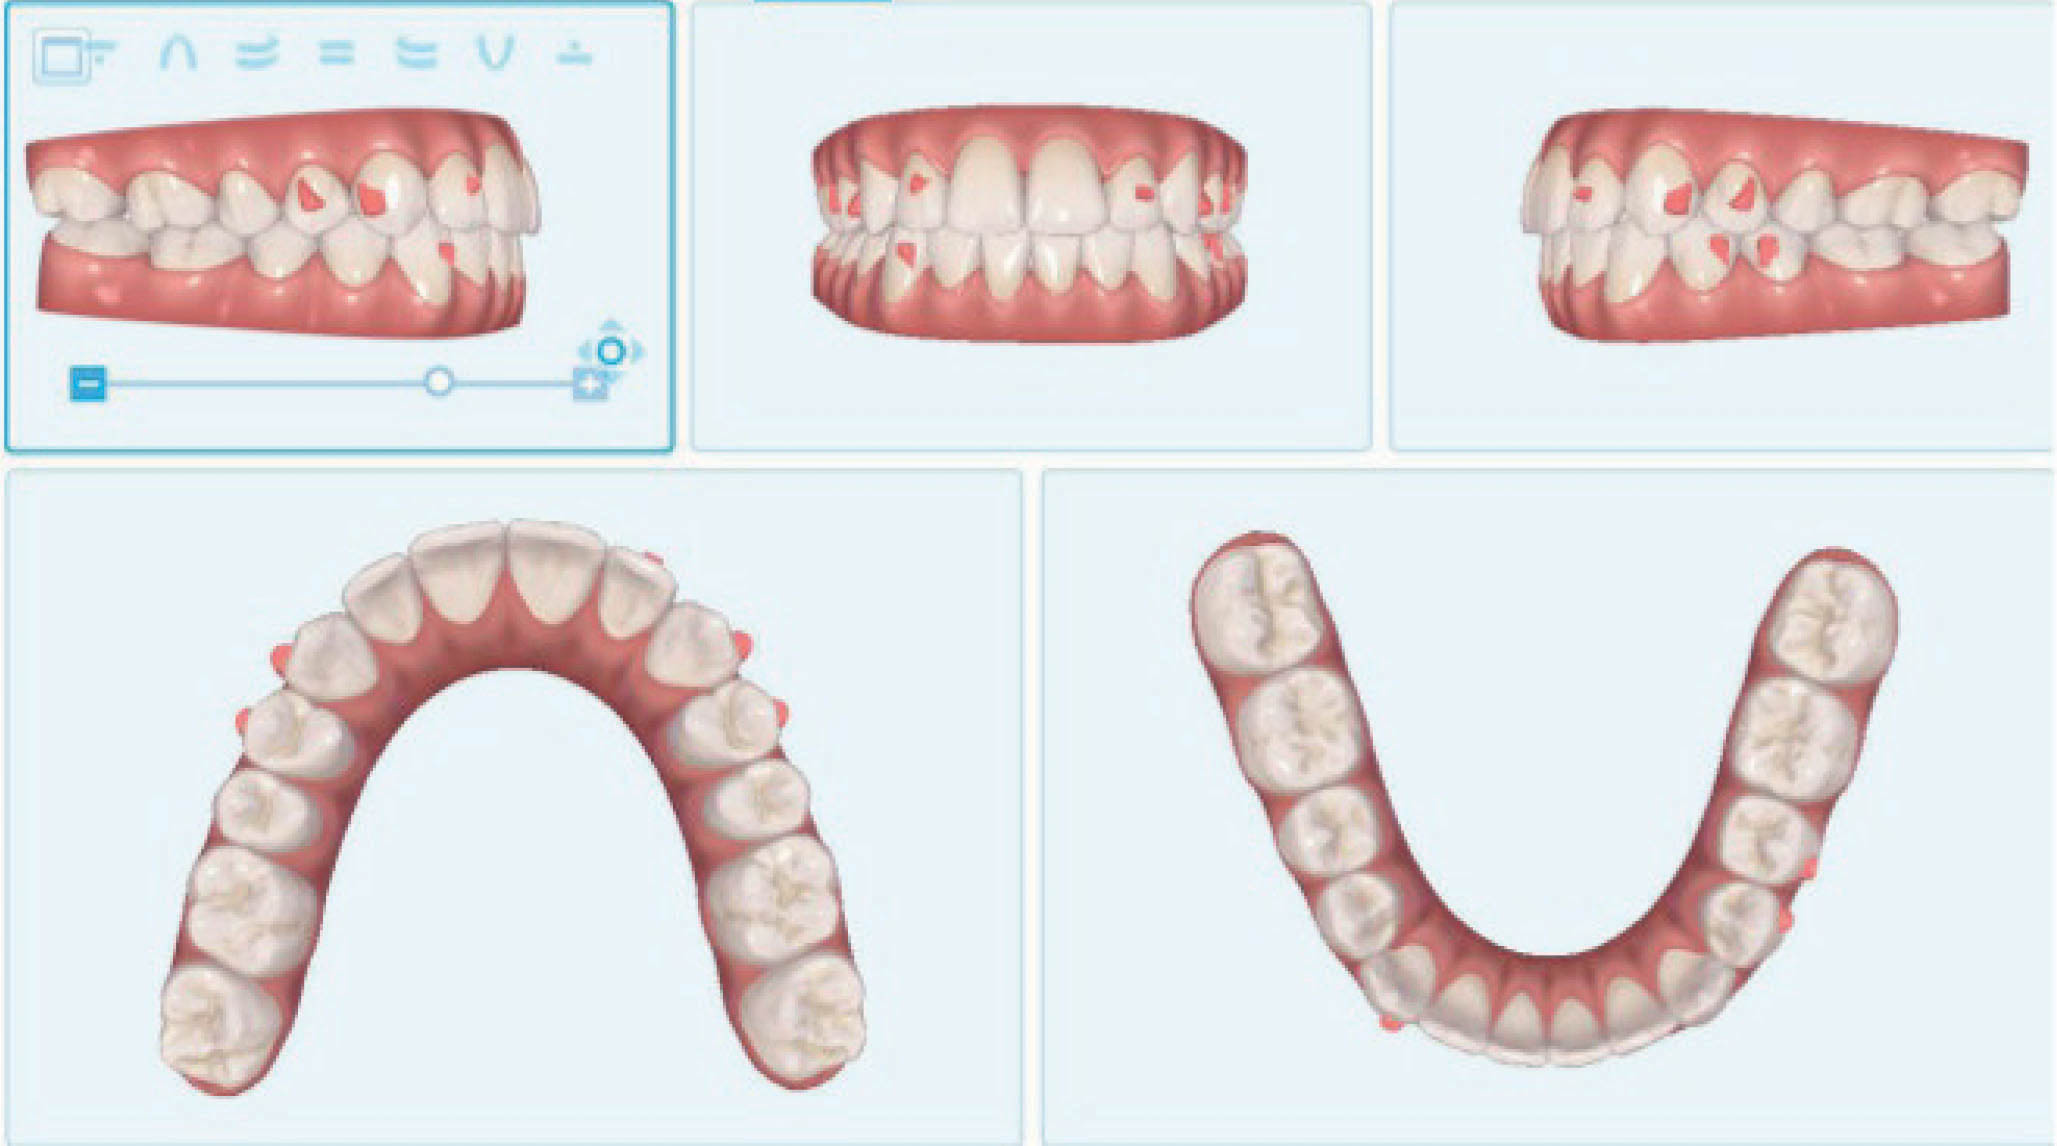

بیمار بعدی یک بیمارکلاسI با میزان متوسطی از کرادینگ در هر دو فک است. به کانینهایی که شدیداً چرخیدهاند دقت کنید (شکل 15-6 تا 17-6). این بیماران به ارتودنسی شفاف عالی جواب میدهند. یک دختر دبیرستانی که نمیخواهد در جشن فارغ التحصیلی خود و عکسهایی که در کلاس میگیرد براکت داشته باشد، خیلی خوب از الاینرهای شفاف استفاده میکند.

شکل 15-6

شکل 16-6

شکل 17-6